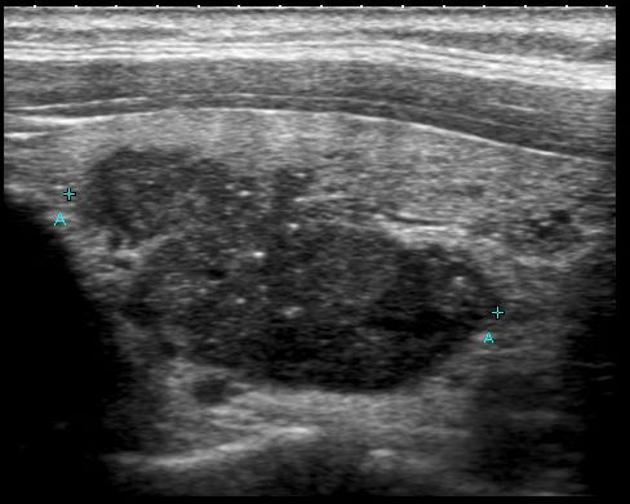

La tecnología de Ultrasonido Hepatobiliar en 2D ha sido la piedra angular durante décadas, proporcionando imágenes bidimensionales de los órganos abdominales. Sin embargo, los recientes avances han llevado esta técnica más allá de la superficie, permitiendo una visualización más profunda y detallada de las estructuras hepáticas y biliares.

La utilización de agentes de contraste con microburbujas ha mejorado significativamente la capacidad de visualización en el Ultrasonido Hepatobiliar. Estas microburbujas mejoran el contraste en las imágenes, permitiendo una detección más precisa de lesiones hepáticas pequeñas y una evaluación más detallada de la vascularización.